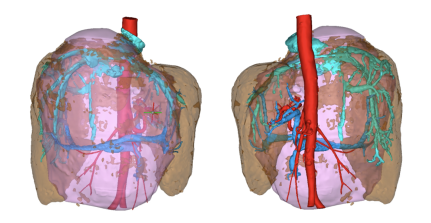

患者术前肝脏三维重建图

治疗已经势在必行,可是方案的选择却让人迟疑。“肝脏的手术没有小手术”,这是肝胆胰外科的专家们常说的一句话。复杂的Glisson系统以及静脉系统在肝实质内四通八达,使整个肝脏如同一个充盈的血窦,术中可能出现致命的出血。郭女士的血管瘤推挤压迫了肝门部血管,左肝蒂可疑位于肿瘤内,手术的难度可见一斑。即使能够安全的将肿瘤切除,对于直径达到18.4cm的巨大占位,术后剩余的肝体积能不能满足患者的生理需要?会不会出现严重的并发症?